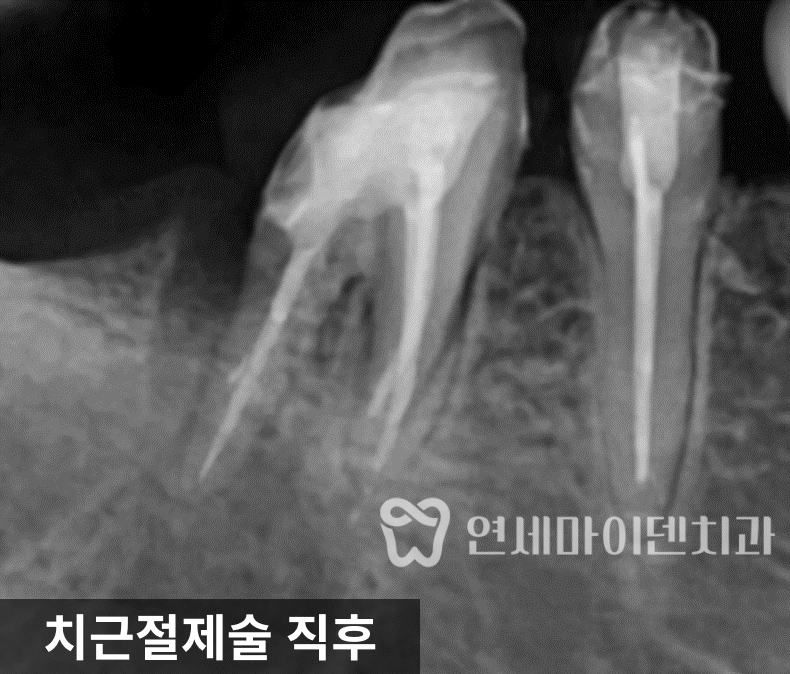

치근(치아 뿌리) 자체의 구조적 문제를 의심해야 합니다.치근절제술

저희는 추가 검사 후, 문제가 되는 부분이

어금니의 뒤쪽 뿌리임을 확인했습니다.다행히 해당 어금니는

두 개의 뿌리로 나뉜 형태(이근성 치아)였기 때문에,문제가 있는 뿌리만 선택적으로 제거하는

치근절제술을 진행할 수 있었습니다.치근절제술은 손상된 뿌리만 제거하고 건강한 부분을 살려

자연치아의 기능을 유지할 수 있는 치료법입니다.

문제가 된 뿌리를 제거한 후, 남은 뿌리를 단단히 보존하고

새로운 보철(크라운)을 씌워 교합을 안정시켰습니다.이후 환자분은 통증 없이

정상적인 식사가 가능한 상태로 회복되었습니다.치근절제술 후 치료과정